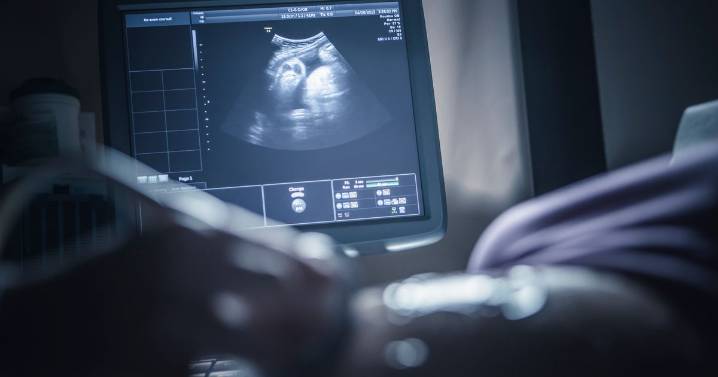

Warning to all pregnant women after 'unsafe procedures' lead to baby deaths

There is a call for tighter regulation as anyone can offer the service